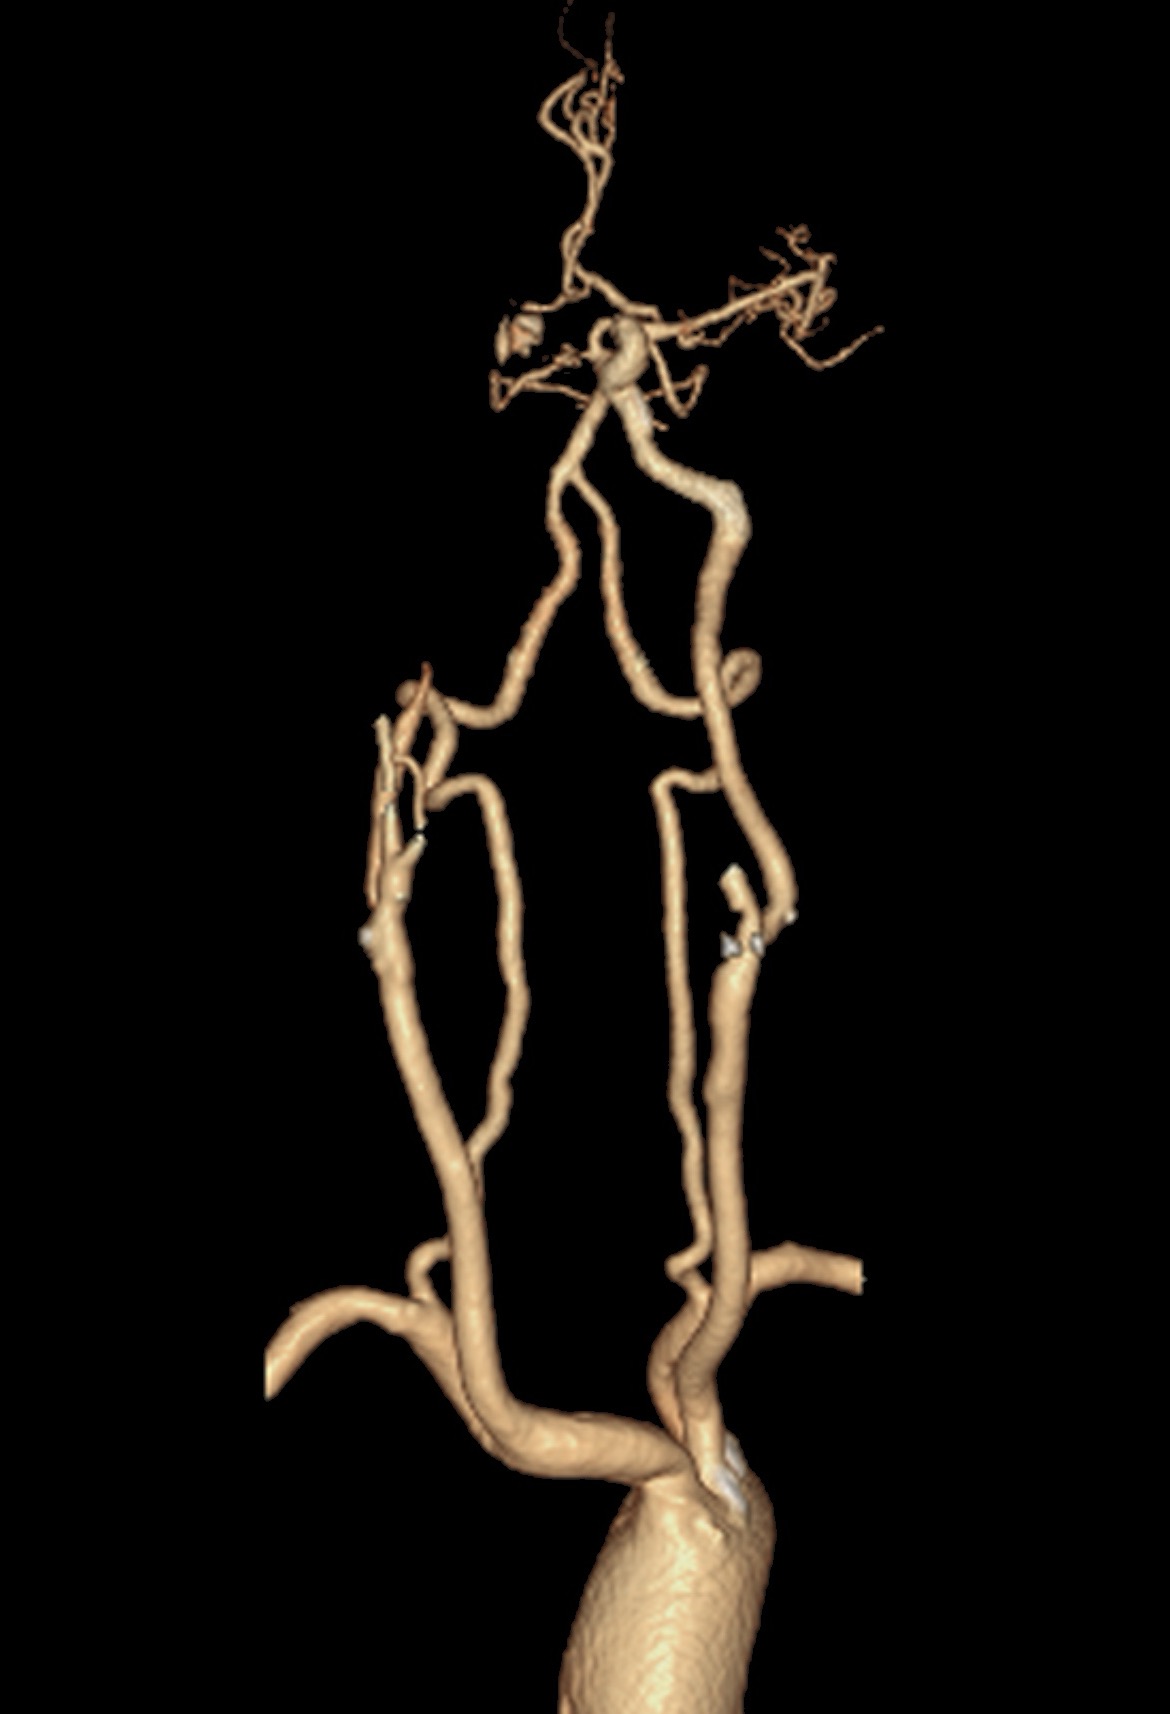

CTA提示右侧颈内动脉及大脑中动脉闭塞